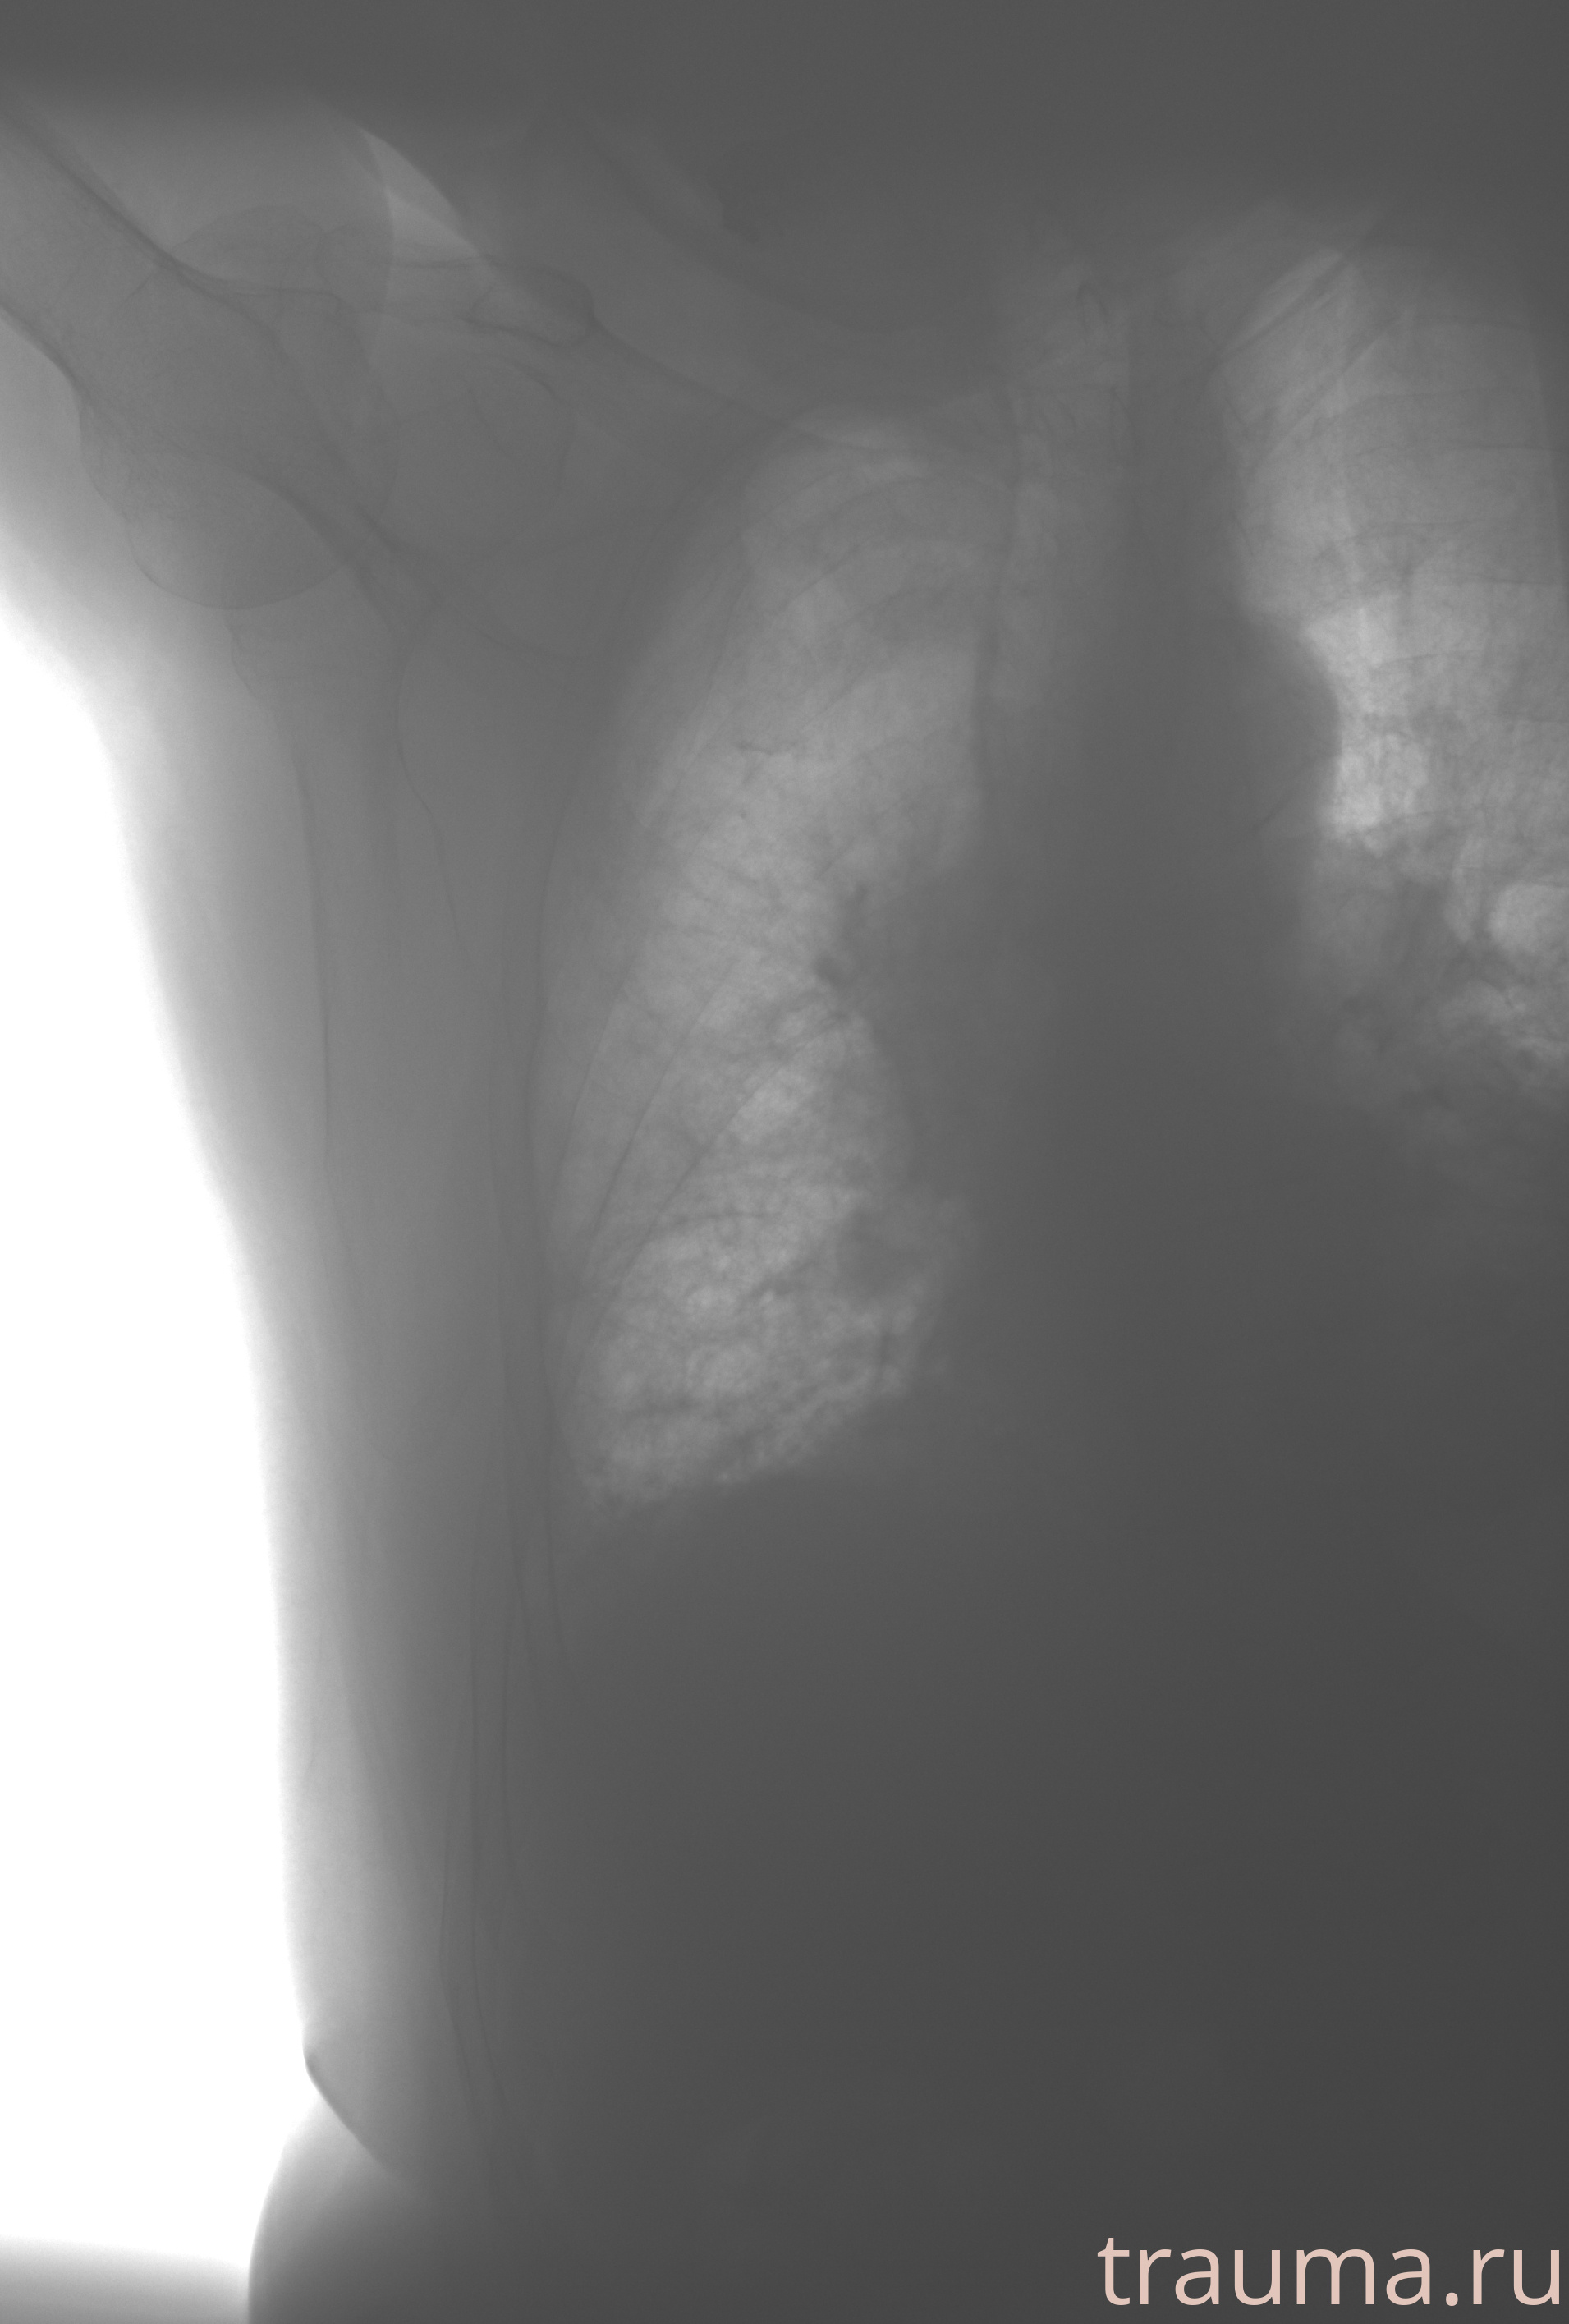

Рентген на дому: по вашему адресу приезжает врач-рентгенолог, травматолог-ортопед с мобильным рентгеновским аппаратом, проводит диагностику травмы или заболевания, делает необходимые рентгенограммы, дает рекомендации по дальнейшему лечению. Получить качественные снимки в домашних условиях возможно благодаря уникальной методике, разработанной МосРентген Центром для института  Склифосовского

при переломе шейки бедра и пневмонии от компании МосРентген Центр - партнера Института имени Склифосовского